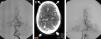

ResultadosSobre 38 pacientes controlados, con una media de seguimiento evolutivo de 61 meses (rango: 6,7-178), la tasa de obliteración confirmada por angiografía/angio-RM fue del 59,5%, con una dosis margen de 14Gy en la gran mayoría de los procedimientos. El 39% de los pacientes recibieron más de un tratamiento de radiocirugía para conseguir el cierre de la malformación. No se observó correlación estadística con la dosis margen, la hemorragia pretratamiento, el diámetro del nido ni la puntuación en el score de Pollock-Flickinger. La tasa de hemorragia anual postratamiento fue de 3,2%; tres pacientes fallecieron por resangrado y la supervivencia actuarial es del 88% a los 5 y 10 años tras el tratamiento. Cuatro pacientes tuvieron nuevos déficits neurológicos transitorios por toxicidad, y solo uno un déficit permanente (2,6%).

ResultsThe obliteration rate confirmed by angiography/MRA was 59.5% on 38 controlled patients. The mean follow-up period was 61 months (range: 6.7-178) and the margin dose was 14Gy in most treatments. Up to 39% of patients received more than one radiosurgery procedure to achieve closure of the malformation. No statistical correlation was found with the margin dose, presence of pretreatment haemorrhage, nidus diameter or score on the Pollock-Flickinger grading system. The annual haemorrhage rate after radiosurgery was 3.2%. Three patients died from rebleeding and actuarial survival rate was 88% at 5 and 10 years after treatment. Four patients suffered new transient neurological deficits due to toxicity, and only one presented a permanent deficit (2.6%).